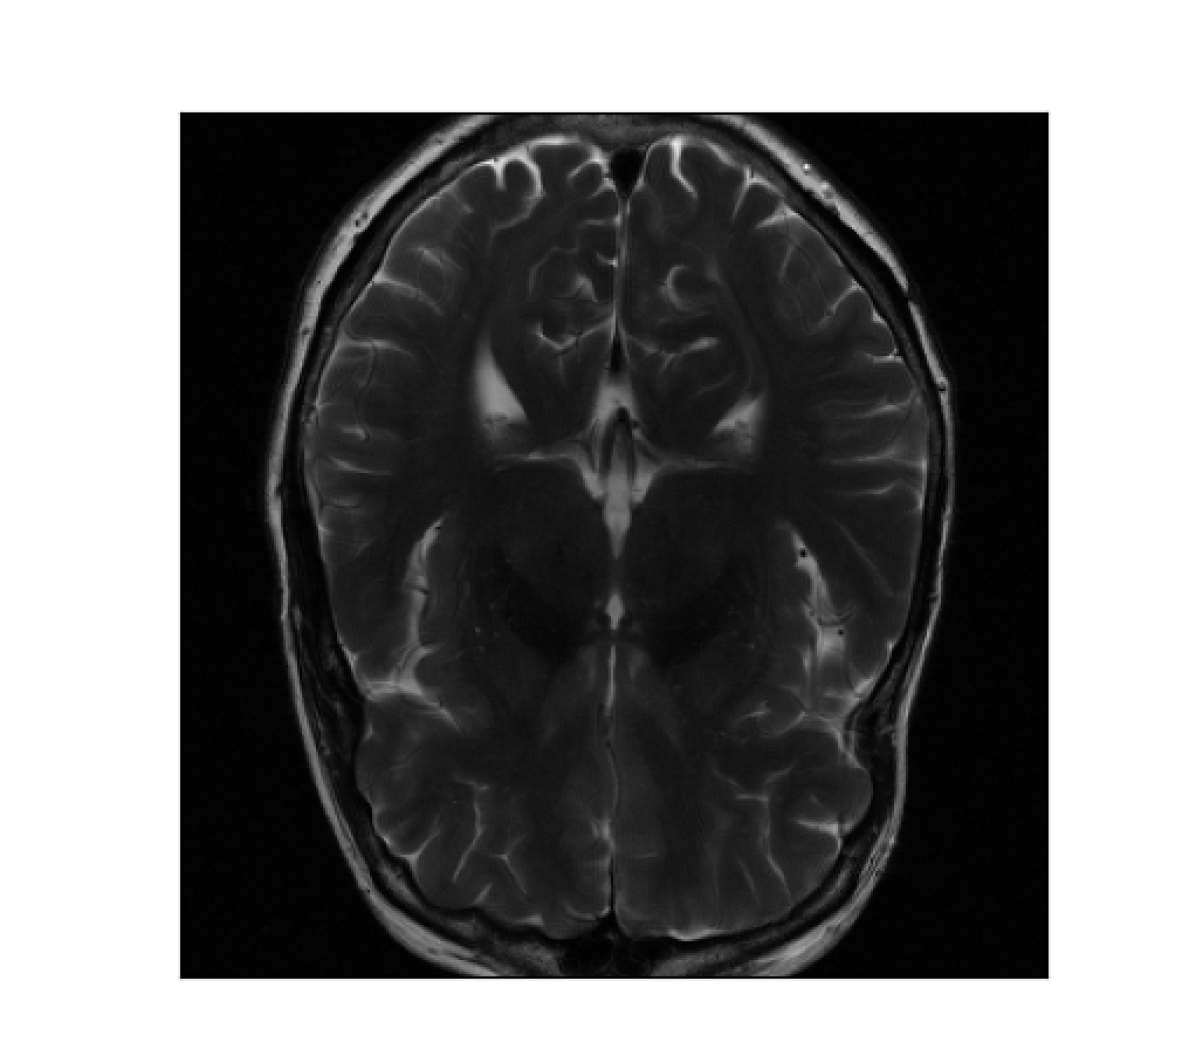

III-B2 Qualitative results

For visual inspection, we present the results of image reconstruction from data undersampled using SPARKLING trajectories generated for various target densities in Fig. 3 (T1subscriptT1\text{T}_{1}-w images) and Fig. 4 (T2subscriptT2\text{T}_{2}-w images). For the sake of space, we only report the best reconstruction results, i.e. with NC-PDNet. For T1subscriptT1\text{T}_{1}-weighted contrast, we show that all methods give similarly performing results, however 𝝆vdssubscript𝝆𝑣𝑑𝑠\boldsymbol{\rm\rho}_{vds} and 𝝆lbsubscript𝝆𝑙𝑏\boldsymbol{\rm\rho}_{lb} provide the best SSIM scores. Further, we observe that in this case, 𝝆vdssubscript𝝆𝑣𝑑𝑠\boldsymbol{\rm\rho}_{vds} is slightly better than 𝝆lbsubscript𝝆𝑙𝑏\boldsymbol{\rm\rho}_{lb}. On the contrary, for T2subscriptT2\text{T}_{2}-w contrast, 𝝆lbsubscript𝝆𝑙𝑏\boldsymbol{\rm\rho}_{lb} outperforms the other densities as reflected both visually in Fig. 4 and quantitatively (see Fig. 2).

Reference T2subscript𝑇2T_{2}-w Image (i) 𝝆vdssubscript𝝆𝑣𝑑𝑠\boldsymbol{\rm\rho}_{vds} (ii) 𝝆sbsubscript𝝆𝑠𝑏\boldsymbol{\rm\rho}_{sb} (iii) 𝝆lsbsubscript𝝆𝑙𝑠𝑏\boldsymbol{\rm\rho}_{lsb} (iii) 𝝆lbsubscript𝝆𝑙𝑏\boldsymbol{\rm\rho}_{lb}

Refer to caption Refer to caption Refer to caption Refer to caption Refer to caption

Figure 4: NC-PDNet-based image reconstruction for retrospective T2𝑇2T2-w imaging with slice 555 in file_brain_AXT2_200_2000019.h5 from validation data in fastMRI dataset for different target sampling densities.